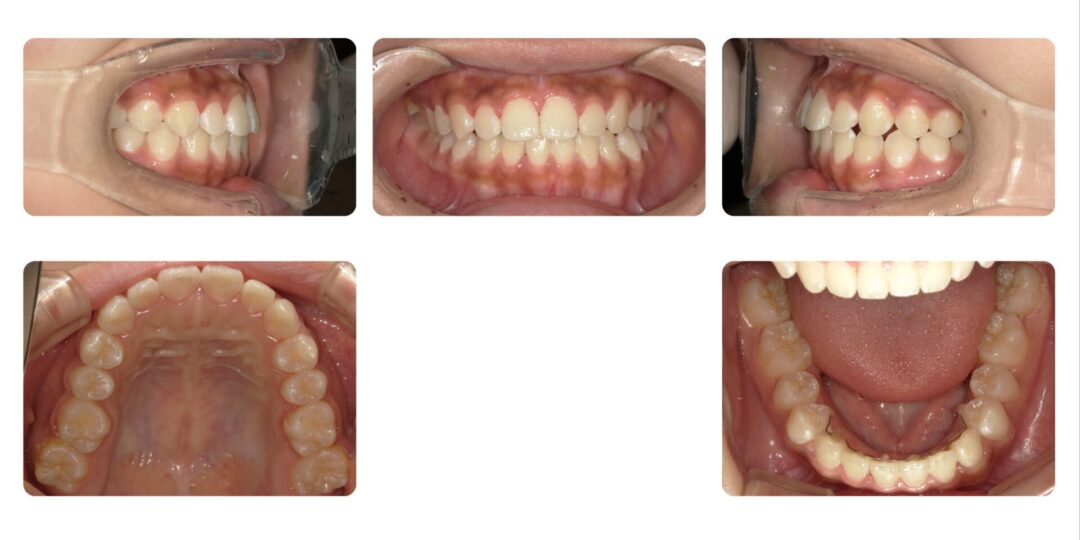

矯正治療後

成人矯正 非抜歯  マルチブラケット矯正

治療期間

1年9ヶ月

治療費用

自由診療 基本料金 審美ブラケット¥770,000、処置料¥5,500

ホワイトワイヤー¥1,100/1本